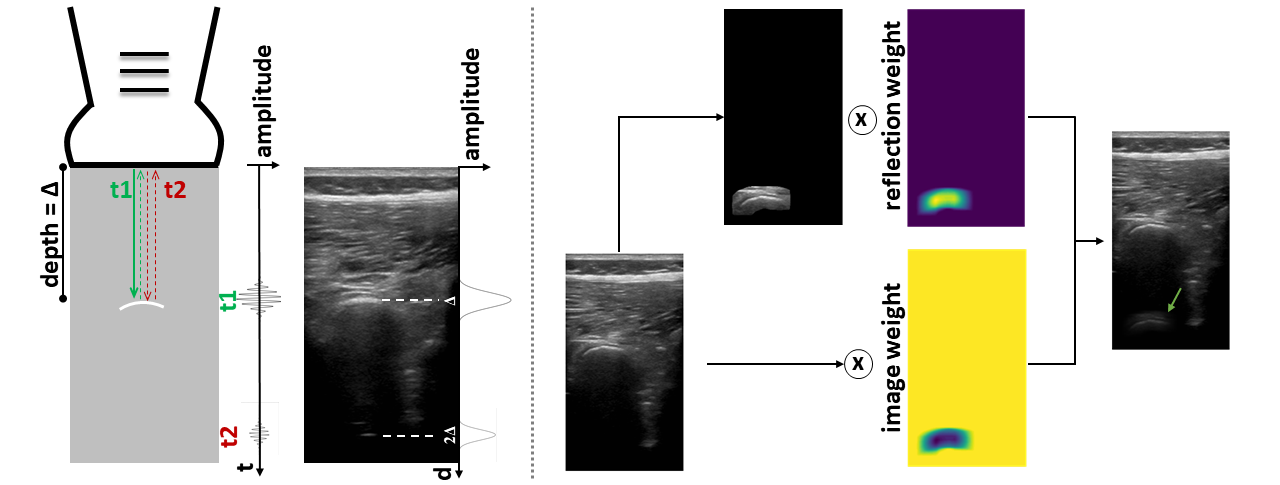

Refer to caption

Figure 4: Reverberation Pipeline. Left: The transmitted signal and the echos generated by a bone at depth ΔΔ\Delta. In the time-amplitude plot the signals generated by the first echo (green arrow) and reverberation echo (red arrow) are reported. The first echo generates a bright area in the B-mode image at ΔΔ\Delta, while the reverberation echo generates an artifact at 2Δ2Δ2\Delta. Right: The generation of reverberation artifacts on B-mode data. The patch containing the bone is extracted and replicated at multiples of ΔΔ\Delta. The replicated patch is weighted and summed up to the original image.

In the proposed method we simulate reverberation artifacts, by first computing the bone centroid (xc,yc)subscript𝑥𝑐subscript𝑦𝑐(x_{c},y_{c}) on the label image. Secondly, we shift the image patch containing the bone along the axially by 2yc2subscript𝑦𝑐2y_{c}. Finally, we compute the resulting image as the weighted sum of the shifted patch and the original image. The multiplication weights for the reverberation region wrsubscript𝑤𝑟w_{r} are defined as the shifted label filtered with a Gaussian filter (kernel size=45 px, sigma=20 px) and scaled by a factor risubscript𝑟𝑖r_{i}, which we call reverberation intensity. The multiplication weights for the original image are defined as 1wr1subscript𝑤𝑟1-w_{r}. The factor risubscript𝑟𝑖r_{i} defines the intensity of the reverberation artifact and is randomly sampled during the augmentation.